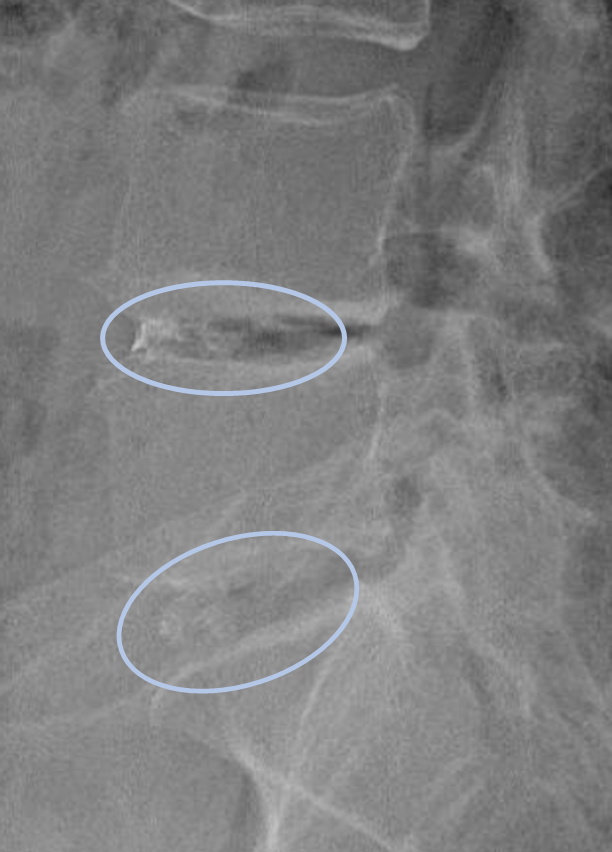

画像及び所見について

- L3/4,4/5,5/s-椎間板変性

- L4/5,5/s-椎間板ヘルニア

以上の事が画像上認められます。

・L4/5,5/s-椎間板ヘルニアを認め、主症状の原因の可能性が高い

DiscoGelを入れた後の画像になります。